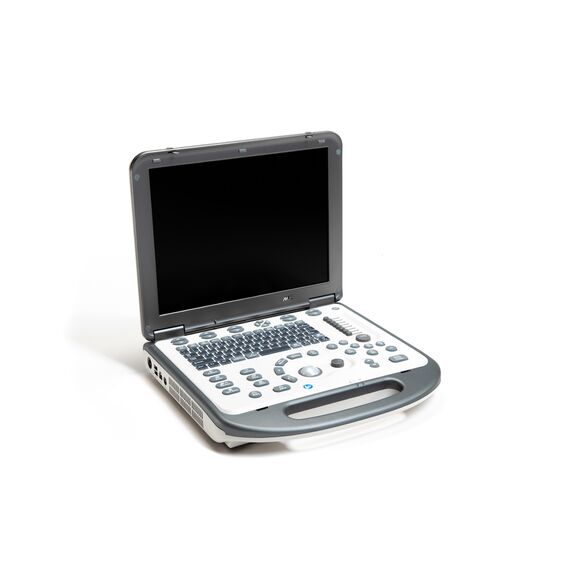

УЗ-сканер Mindray М6 exp представляет собой полнофункциональную портативную, размером с ноутбук, систему цветной допплерографии. Аппарат обеспечивает безупречную визуализацию в формате 2D. Оснащенная специализированными технологиями система М6 exp является оптимальным вариантом для применения.

Характеристики

Тип

- Портативный

Класс

Средний

Количество активных разъемов для датчиков

1

Линейка

M